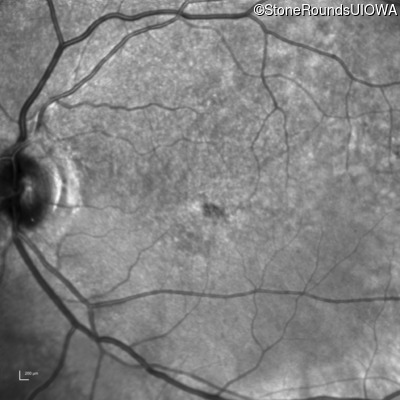

Infrared Fundus Photograph - Right - 20/100 -2 sc

Exemplar